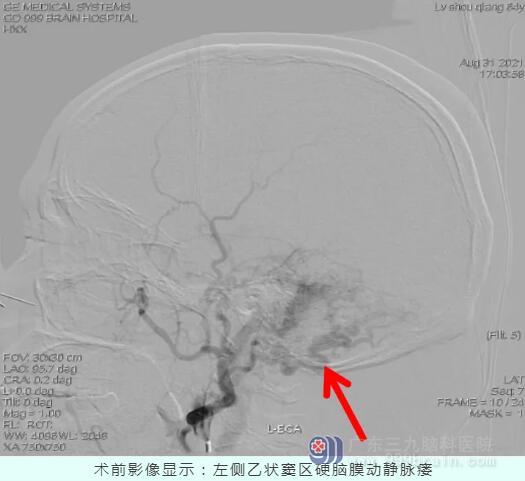

结合检查结果,王展航发现,卢伯的症状是由一种少见的脑血管病——硬脑膜动静脉瘘引起。这种脑血管病是由于脑部动静脉之间“短路”,会导致颅内血管杂音。“患者的耳鸣实则是颅内血管杂音。”持续性的轰鸣音是常见的临床表现,颅内血管杂音的程度与硬脑膜的血流量及部位有关。

明确病因后,王展航邀请神经介入科主任王培明为患者会诊,讨论后一致建议手术治疗。

硬脑膜动静脉瘘是属于硬脑膜动静脉畸形的一种情况,硬脑膜动静脉瘘主要是由于硬脑膜动静脉或者颅内其他的动静脉出现了瘘洞,因此称为硬脑膜动静脉瘘。王展航介绍,患者除了会出现类似耳鸣的颅内杂音外,由于动静脉畸形,患者通常还会出现局部脑供血不足,从而表现出头痛症状,病情严重时甚至会出现颅内出血。另外,头晕、偏瘫、视力下降、眼球运动神经障碍等也是该病的常见症状。